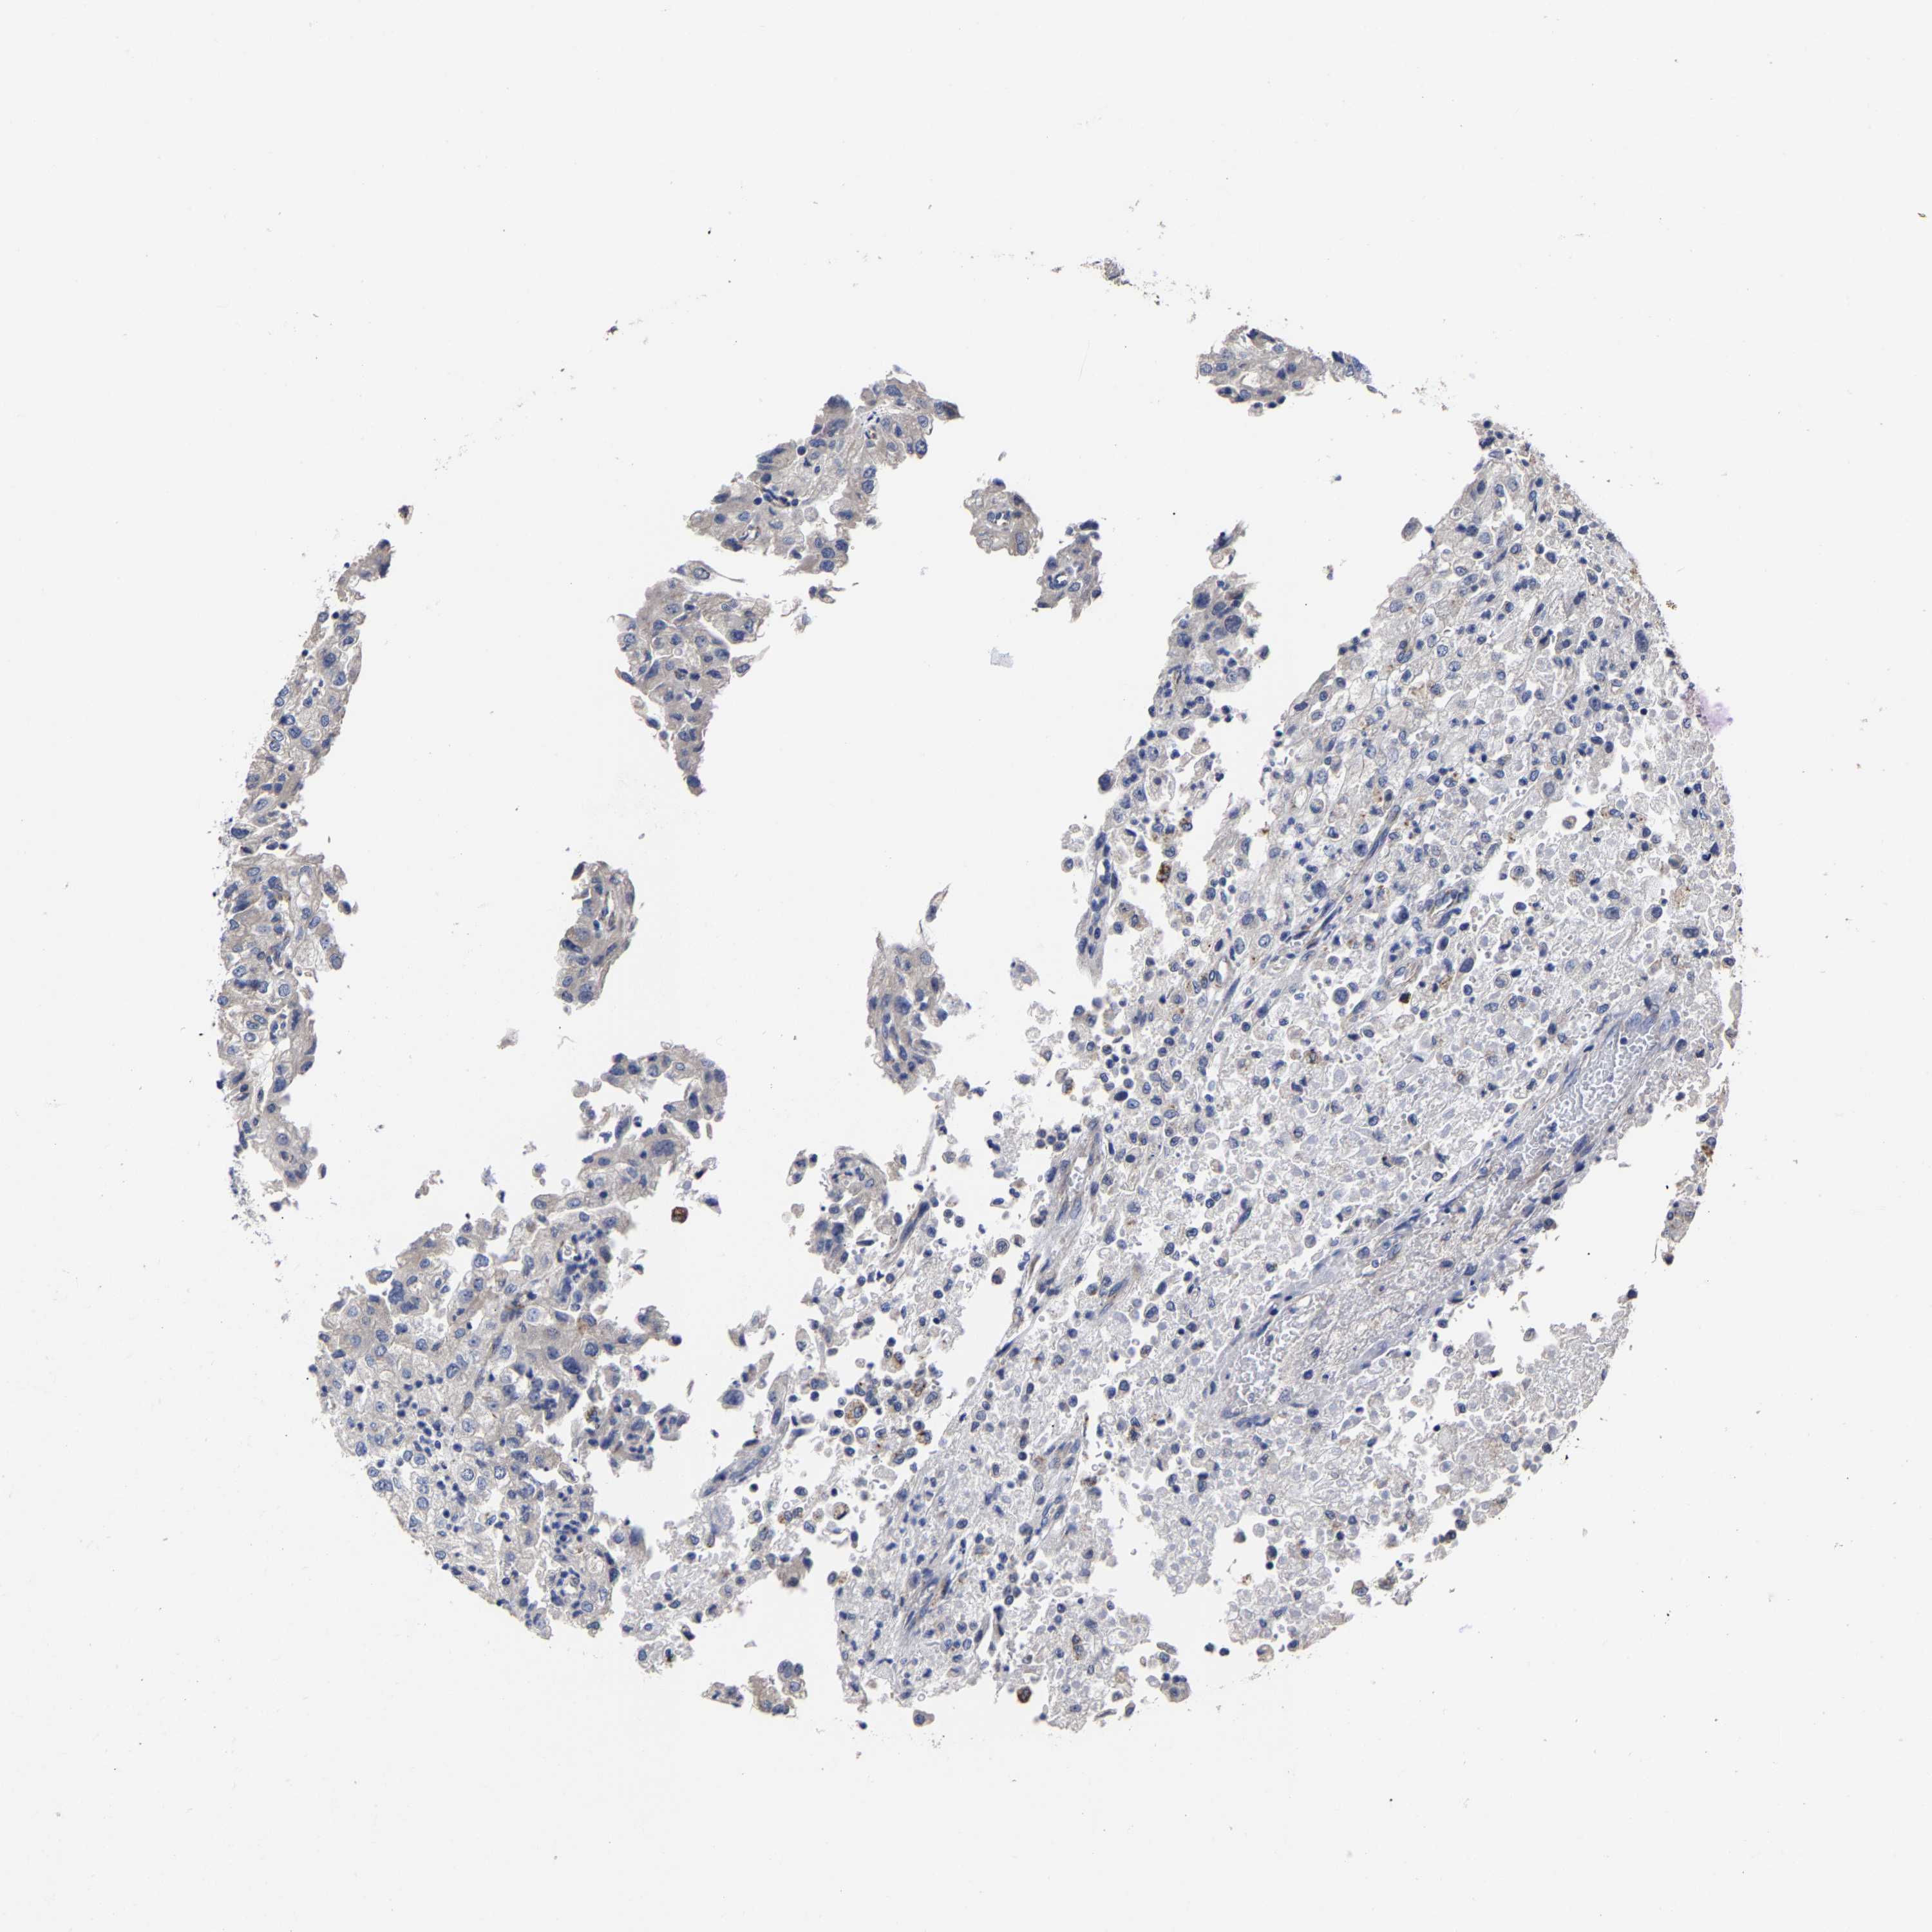

KIDNEY RENAL CLEAR CELL CARCINOMA (TCGA) - Interactive survival scatter ploti

The Survival Scatter plot shows the clinical status (i.e. dead or alive) for all individuals in the patient cohort, based on the same data that underlies the corresponding Kaplan-Meier plots. Patients that are alive at last time for follow-up are shown in blue and patients who have died during the study are shown in red.

The x-axis shows the expression levels (FPKM) of the investigated gene in the tumor tissue at the time of diagnosis. The y-axis shows the follow-up time after diagnosis (years). Both axes are complimented with kernel density curves demonstrating the data density over the axes. The top density plot shows the expression levels (FPKM) distribution among dead (red) and alive patients (blue). The right density plot shows the data density of the survived years of dead patients with high and low expression levels respectively, stratified using the cutoff indicated by the vertical dashed line through the Survival Scatter plot. This cutoff is automatically defined based on the FPKM cutoff that minimizes the p-score. The cutoff can be changed by dragging the vertical line or by entering a cutoff value in the square labeled "Current cut-off".

Under the Survival Scatter plot the p-score landscape (black curve; left axis) is shown together with dead median separation (red curve; right axis). Dead median separation is the difference in median mRNA expression between patients who have died with high and low expression, respectively. It is calculated as follows: median FPKM expression of dead patients with high expression - median FPKM expression of dead patients with low expression. This is intended to aid the user in visually exploring custom cutoffs and the associated p-scores and dead median separation.

Individual patient data is displayed and can be filtered by clicking on one or more of the category buttons on the top of the page. Categories describing expression level and patient information include: high, low, alive, dead, female, male and tumor stages. The scale of the x-axis can be toggled between linear and log-scale by clicking on the "x log" button. Mouse-over function shows TCGA ID, patient information and mRNA expression (FPKM) for each patient.

& Survival analysisi

Kaplan-Meier plots summarize results from analysis of correlation between mRNA expression level and patient survival. Patients were divided based on level of expression into one of the two groups "low" (under cut off) or "high" (over cut off). X-axis shows time for survival (years) and y-axis shows the probability of survival, where 1.0 corresponds to 100 percent.

AASS is not prognostic in Kidney Renal Clear Cell Carcinoma (TCGA)

Best expression cut offi

Based on the FPKM value of each gene, patients were classified into two groups and association between prognosis (survival) and gene expression (FPKM) was examined. The best expression cut-off refers the FPKM value that yields maximal difference with regard to survival between the two groups at the lowest log-rank P-value. Best expression cut-off was selected based on survival analysis .

When clicking on this number, the vertical dashed line indicating cut-off, the interactive survival plot, and the Kaplan-Meier curve will be adjusted to show results based on the best expression cut-off.

: 2.95

P scorei

Log-rank P value for Kaplan-Meier plot showing results from analysis of correlation between mRNA expression level and patient survival.

N/A

5-year survival highi

5-year survival for patients with higher expression than the expression cutoff.

For melanoma and glioma, 3-year survival is shown.

5-year survival lowi

5-year survival for patients with lower expression than the expression cutoff.

TCGA RNA samplesi

RNA-seq data is reported as average FPKM (number Fragments Per Kilobase of exon per Million reads), generated by the The Cancer Genome Atlas (TCGA) .

Normal distribution across the dataset is visualized with box plots, shown as median and 25th and 75th percentiles. Points are displayed as outliers if they are above or below 1.5 times the interquartile range. FPKM values of the individual samples are presented next to the box plot.

Average pTPM 3.6

Number of samples 521